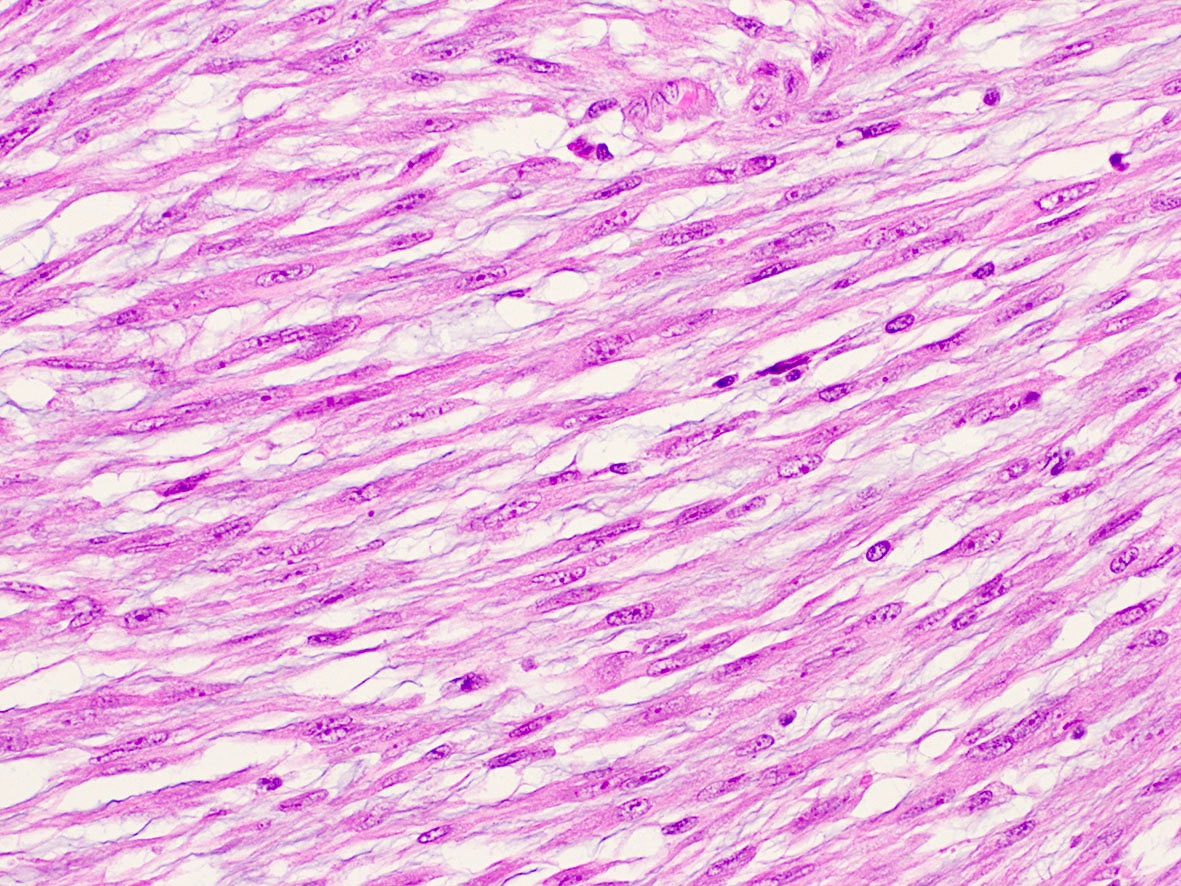

Microscopic (histologic) images

Contributed by A. Cristina Vargas, M.B.B.S., Ph.D., Patricia Guzman, M.D., Fiona Bonar, M.B.B.Ch., Alison Cheah, M.B.B.S. and Martin Jones, M.B.B.S.

Practice question #1

What is the expected diagnosis for a uterine spindle cell tumor with this histological appearance? The tumor displayed focal smooth muscle expression, strong ALK overexpression on IHC and an ALK translocation was confirmed by FISH.

- Endometrial stromal sarcoma

- Epitheliod myofibroblastic sarcoma

- Inflammatory myofibroblastic tumor

- Leiomyoma

- Spindle cell tumor (S100+ / SOX10- / CD34+) with ALK translocations

Practice answer #1